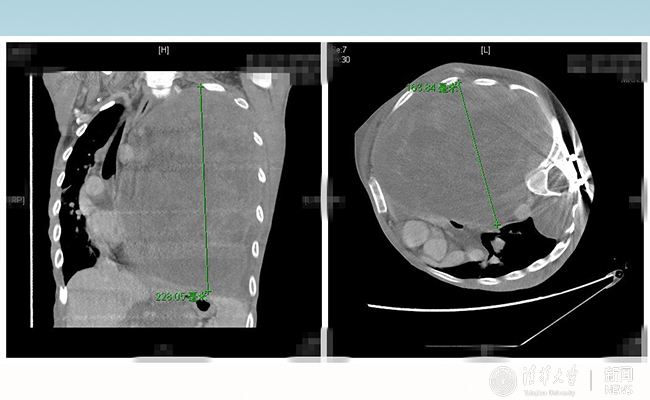

2016.10清华长庚多学科助力胸外科成功切除巨型神经纤维瘤

清华长庚医院多学科助力胸外科手术,成功帮28岁的患者“小飞”切除巨型神经纤维瘤,帮助重病的患者重生。